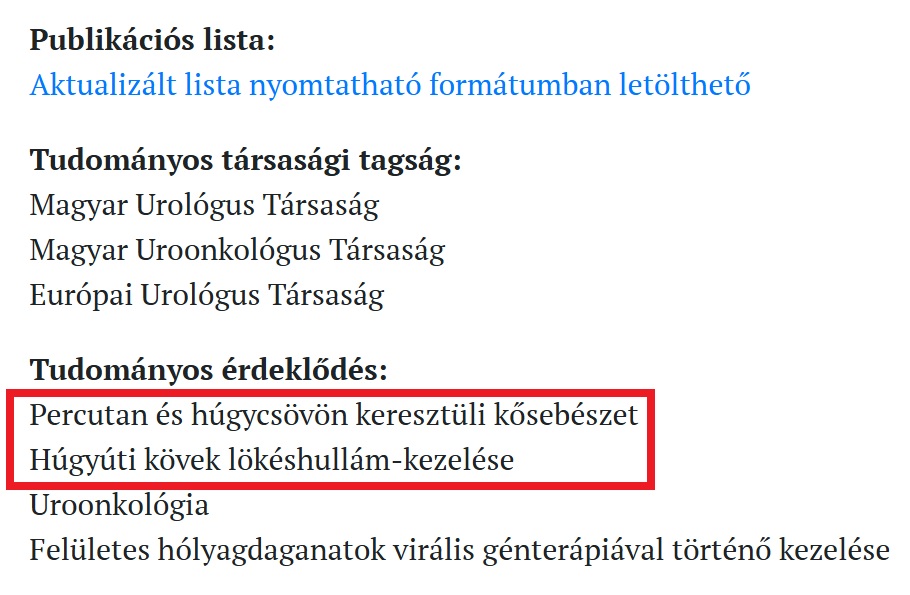

Másnap (Dec.12.) pont az Urológiai klinikára ment, vitte a fenti leletet, Dr Horváth András urológus lejegyezte az értéket, de ezen kívül semmit nem kommunikált és antibiotikumot nem adott! Az orvos távozóban még utánunk kiáltott, hogy „Nem jó helyen járnak, én onkológus vagyok”. Mi van? Ez hogy jön ide? – kérdezte tőlem Zsolt. Lehet, hogy onkológus is, de épp a keddenkénti urológiai rendelését tartotta, és fő érdeklődési területének ő maga a vesekövességet írta le. Itt a bizonyíték a SE honlapjáról: